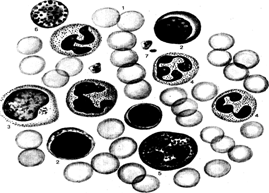

Рис. Клетки периферической крови человека.

1 тАУ эритроциты, 2- лимфоциты, 3- моноциты, 4 тАУ нейтрофильные гранулоциты, 5 тАУ эозинофильные гранулоциты, 6 тАУ базофильные гранулоциты, 7 тАУ тромбоциты.